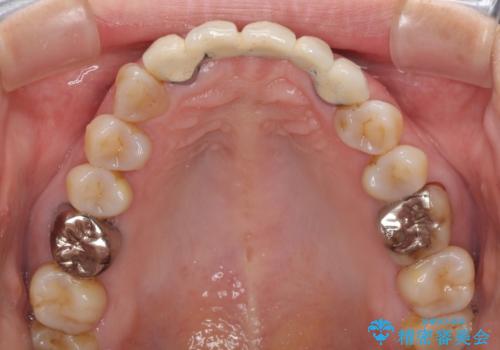

- アンバランスな色や形、歯肉ラインの黒い縁が目立ってしまったブリッジの作り直しを希望して来院された患者様です。

自然な仕上がりとするため、金属を使用しないオールセラミックブリッジにより補綴治療を行うこととしました。

装着されていたブリッジは、支台となっている歯と欠損している歯で色が大きく異なっていましたが、オールセラミックとしたことで、全体的に色調の整った仕上がりとなりました。

歯肉ラインがきれいに整い、患者様には大変満足していただきました。